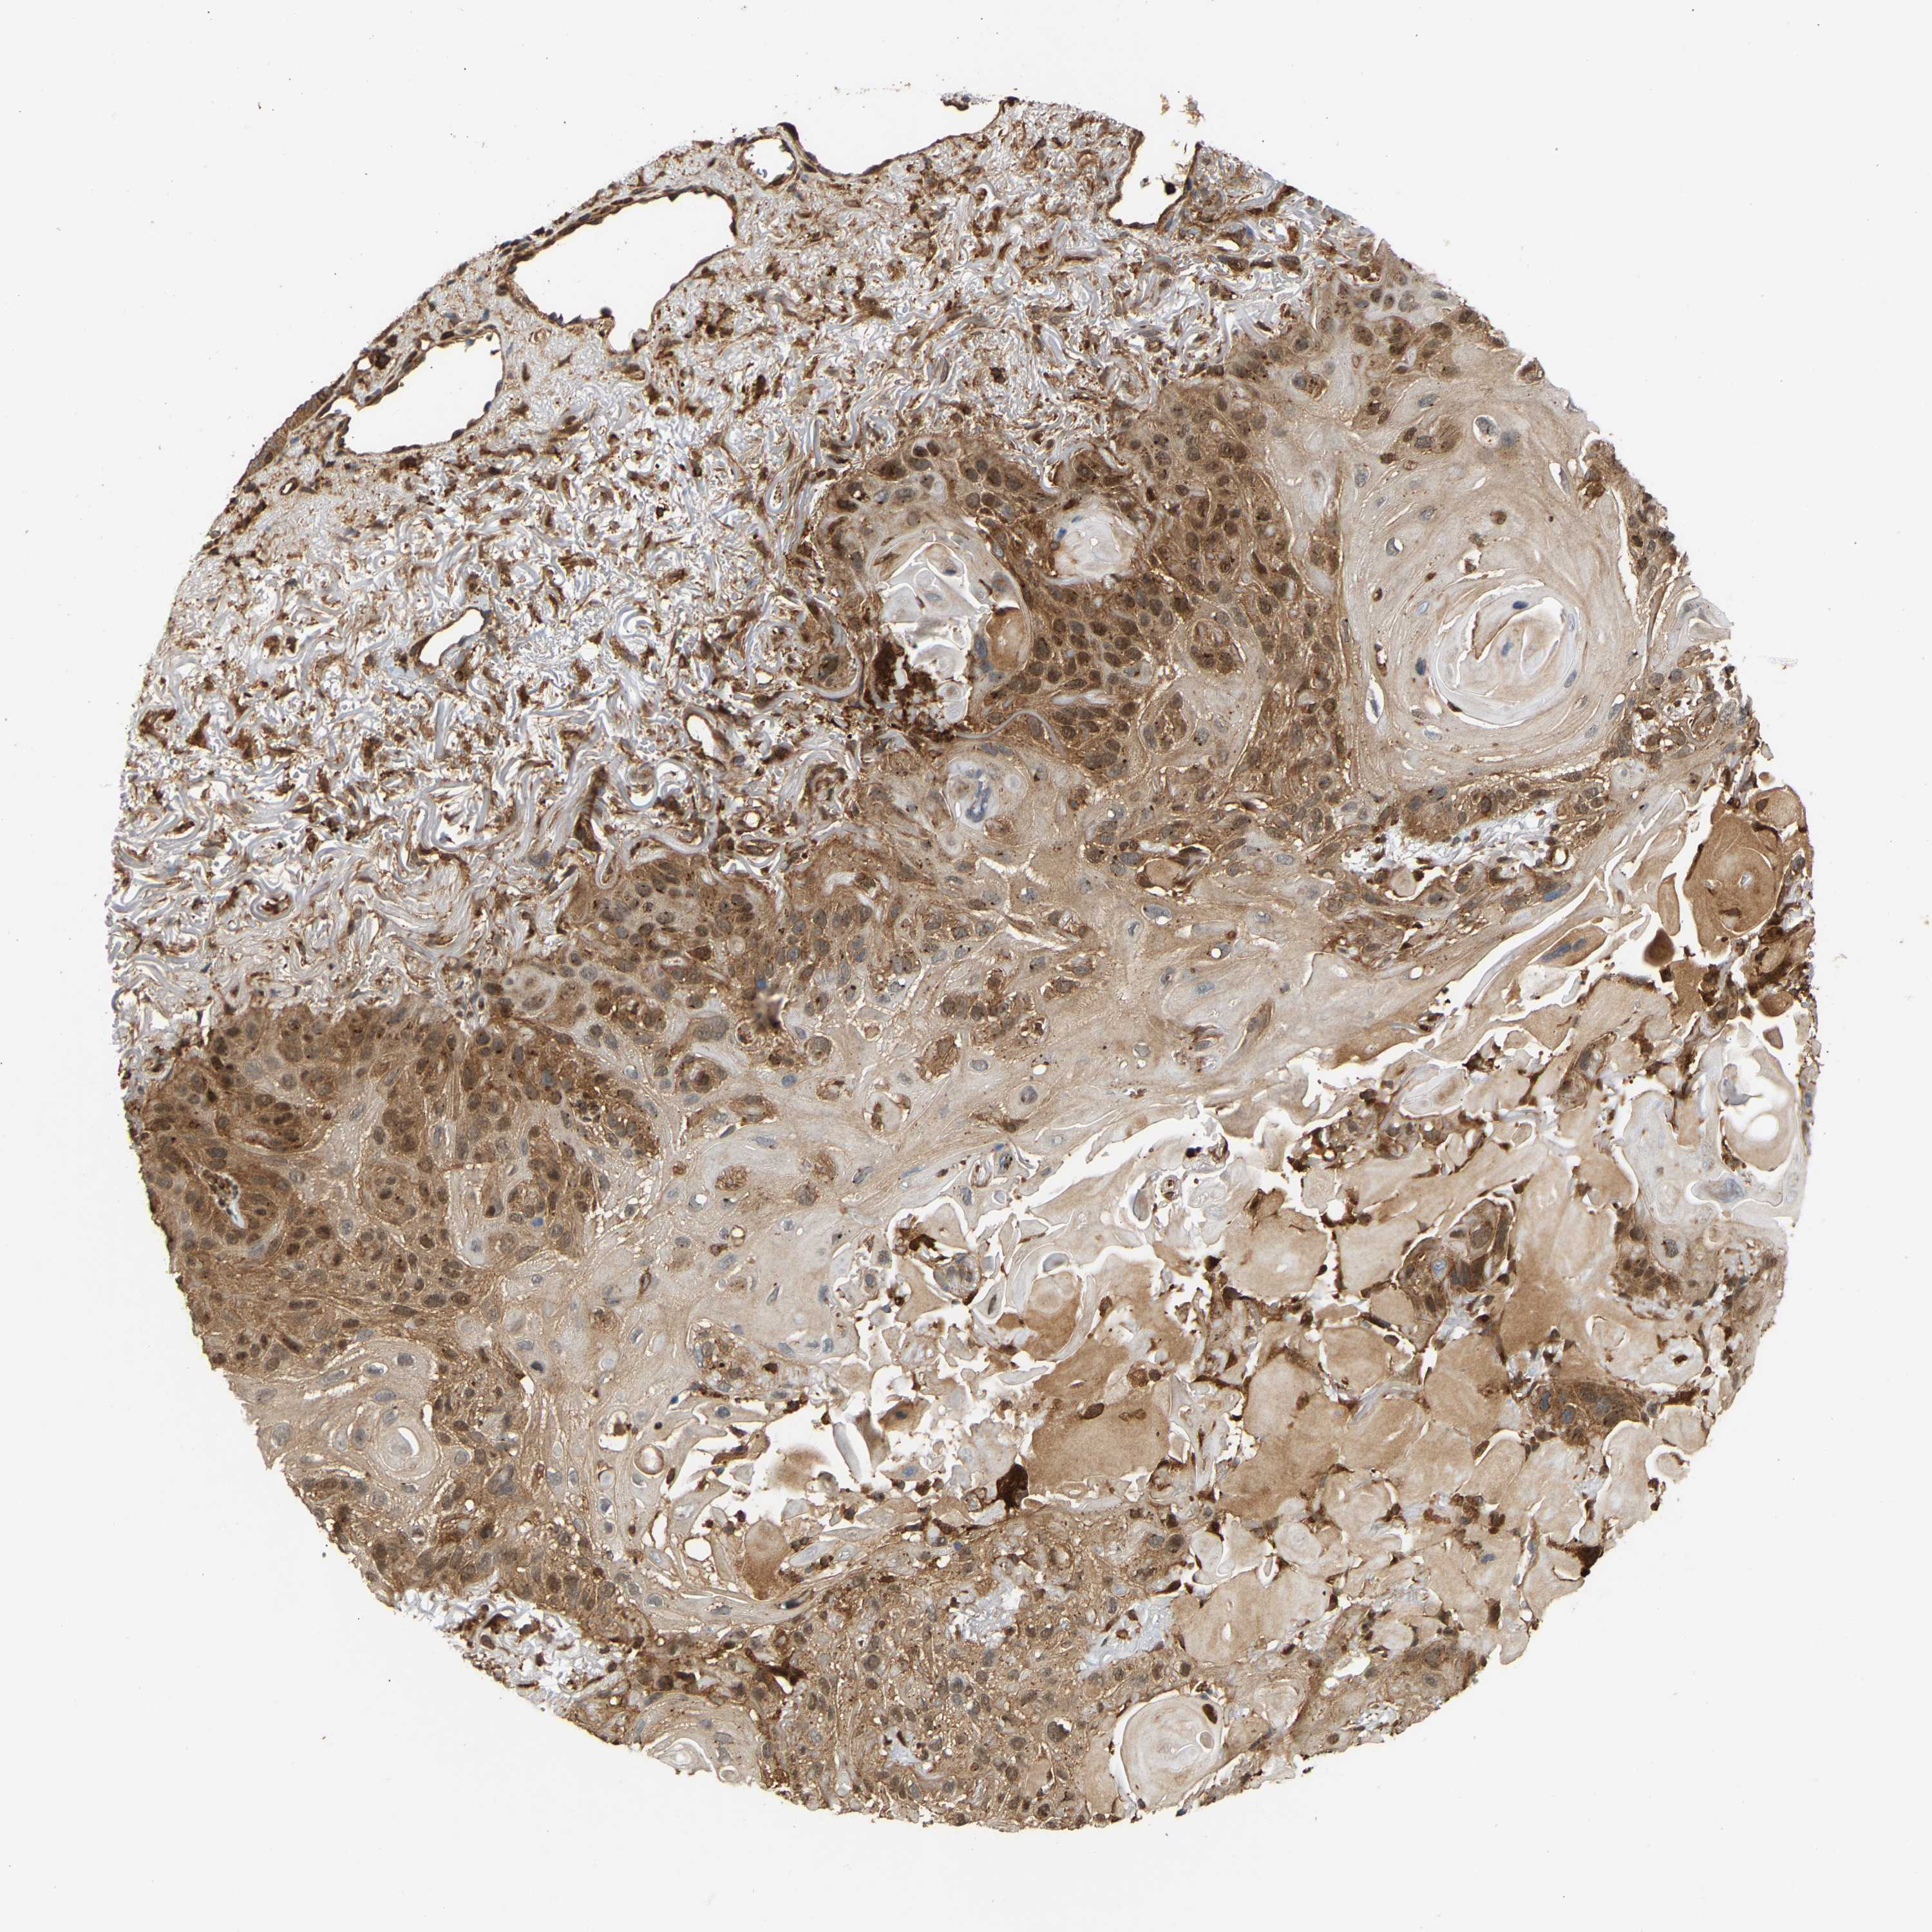

CANCER SKIN CANCER Show tissue menu

Basal cell and squamous cell cancer

SKIN CANCER - Protein expressioni

A mouse-over function shows sample information and annotation data. Click on an image to view it in a full screen mode. Samples can be filtered based on level of antibody staining by selecting one or several of the following categories: high, medium, low and not detected. The assay and annotation is described here.

Each image is clickable and will lead to virtual microscopy that enables deeper exploration of all samples and also displays staining intensity scores, fraction scores and subcellular localization as well as patient and tissue information for each sample.

Antibody HPA019477

Antibody HPA024018

Basal cell carcinoma

Squamous cell carcinoma, NOS

Squamous cell carcinoma, metastatic, NOS